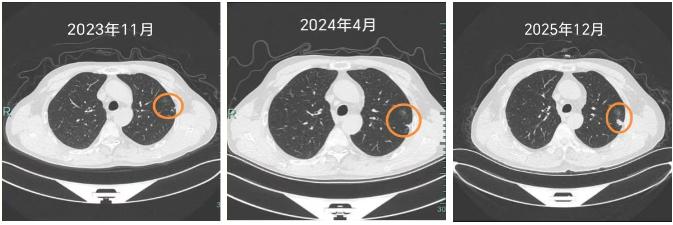

老杨是个地道的“老烟枪”,三十多年的烟龄,手指头都被熏得焦黄。直到两年前他才把烟戒了,因为那时单位体检,在他左下肺发现了一个磨玻璃结节。老杨心里一慌:“大夫,这不会是癌吧?”

“除了戒烟,还要记得定期复查,有什么不舒服的也能及早治疗。”医生提醒老杨。而接下来的两年复查中,老杨的左上肺出现了明显的实性结节,并有胸膜牵拉表现,提示恶性可能。他再次选择来到医院心胸外科就诊。

“有些早期肺癌,就像埋在土里的种子,第一颗被我们挖掉了,但土壤里可能还藏着另一颗,或者因为长期吸烟造成的‘坏环境’,让新的种子在别处发芽了。”心胸外科专家团队为老杨详细解释了他的病况,安抚了他焦虑的心情,很快便开展了胸腔镜下左上肺亚肺叶切除术,标本可见明显的胸膜凹陷,剖开可见两枚结节。最终病理明确诊断:是腺癌!

吸烟带来的伤害是具有累积效应的,定期复查胸部CT在肺结节早期发现,早期治疗中有着重要的意义,绝大多数的早诊早治的患者可以有非常良好的长期获益。远离烟草,就是对健康的直接投资,戒烟后,肺部细胞不在承受新的攻击,炎症开始消退,修复功能开始恢复,患癌风险比起继续吸烟者也持续降低。